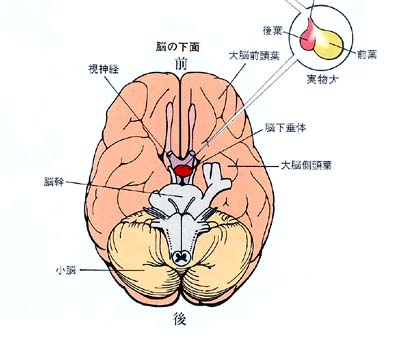

脳下垂体はどこにあるのか?とよく聞かれますが、およそ首から上のいわゆる頭蓋骨のほぼ中心に位置します。別のいい方をすれば、眉間の奥7cm前後のところにあります。

脳下垂体のすぐ中上には左右の視神経とその交叉部があります。また、脳下垂体の左右には海綿静脈洞という太い静脈があり、その中を内頸動脈という太い動脈や眼球を動かす神経などが走っています。正常な脳下垂体は 「女性の小指の先端」くらいの大きさで、重さは1gもありません。 これはさらに前葉と後葉の2部に分かれており、前者が大きな容積を占めています。

脳下垂体の近傍には、腺腫以外にも頭蓋咽頭腫、ラトケ嚢胞、胚細胞腫、髄膜腫といった様々な腫瘍が発生します。これらは腺腫と似たような症状を示しますが、CTスキャンやMRI等の画像診断で鑑別が可能です。